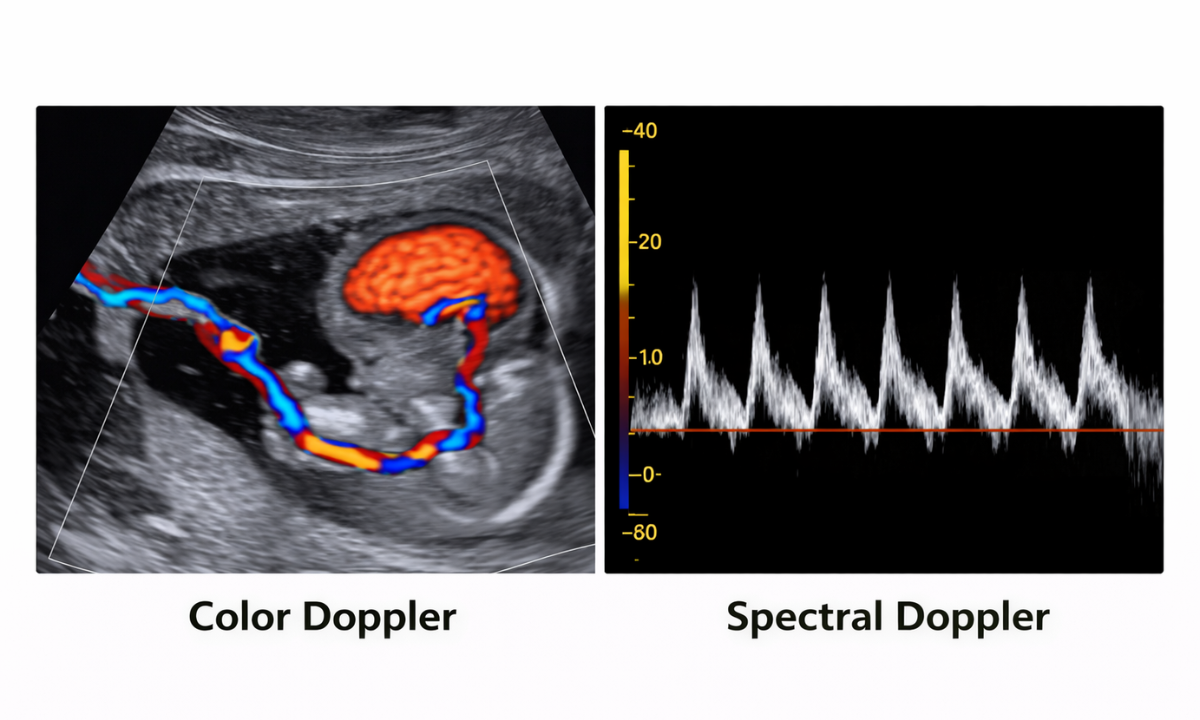

There are mainly two types used during pregnancy, and each serves a slightly different purpose in assessing your baby’s well-being:

Color Doppler

• Shows blood flow using different colours (usually red and blue)

• Helps visualise circulation patterns clearly in real time

• Makes it easier for doctors to identify blockages, reduced flow, or abnormal circulation in the placenta and umbilical cord

Spectral Doppler

• Displays blood flow as waveforms on a graph

• Helps measure the speed, direction, and resistance of blood flow

• Provides detailed numerical values that doctors use to assess whether the blood supply is normal or needs closer monitoring

Both are equally safe and non-invasive, and doctors often use them together for a more comprehensive evaluation, depending on what needs to be assessed in your pregnancy.